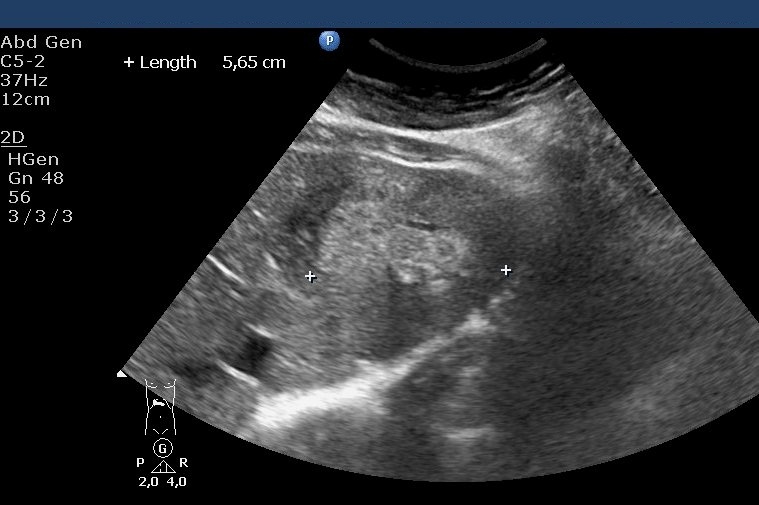

Besides these forms, metastases with mixed echostructure (containing both hyperechoic and hypoechoic areas) and cystic metastases with necrotic content can occur relatively often (Figure 24).

Figure 24: Metastases of a GIST tumour, US

The liver metastases of colorectal origin are usually characterised by a bit inhomogeneous hyperechoic structure sorrounded by a hypoechoic rim. (Figure 25)

Figure 25: Liver metastasis of rectal cancer, US

In the central area of bigger (4-6 cm in diameter) metastases necrosis can also develop as so called „target” form (or commonly called as bull’s eye sign).